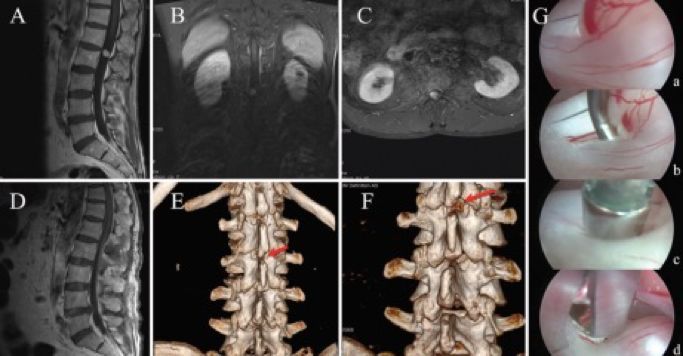

接诊后,朱主任对阿姨进行了初步检查,建议她做一个腰椎磁共振检查,发现腰椎椎管内有一个1.5cm大小的肿瘤,专业名称是“腰椎椎管内神经鞘瘤”。

我们神经脊柱团队经过周密的病情分析,运用先进的显微镜、内镜联合微创手术方式,在磁共振影像导航的支持下,精确定位肿瘤位置,采用很小的创面,在充分保护脊柱自身稳定性的前提下,应用人体自身的脊柱骨骼间隙,完整切除肿瘤,并最大程度的保护脊柱骨骼的完整性。